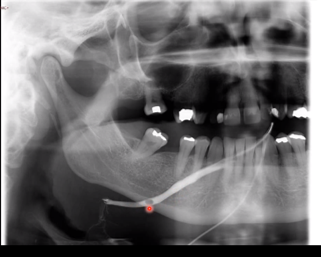

Describe this contrast image finding

• Sialography procedure or right submandibular gland

• See the contrast thoughout the duct and see a blockage about 80% of way through

• The salivary stone is being passed through the duct causing temp obstruction